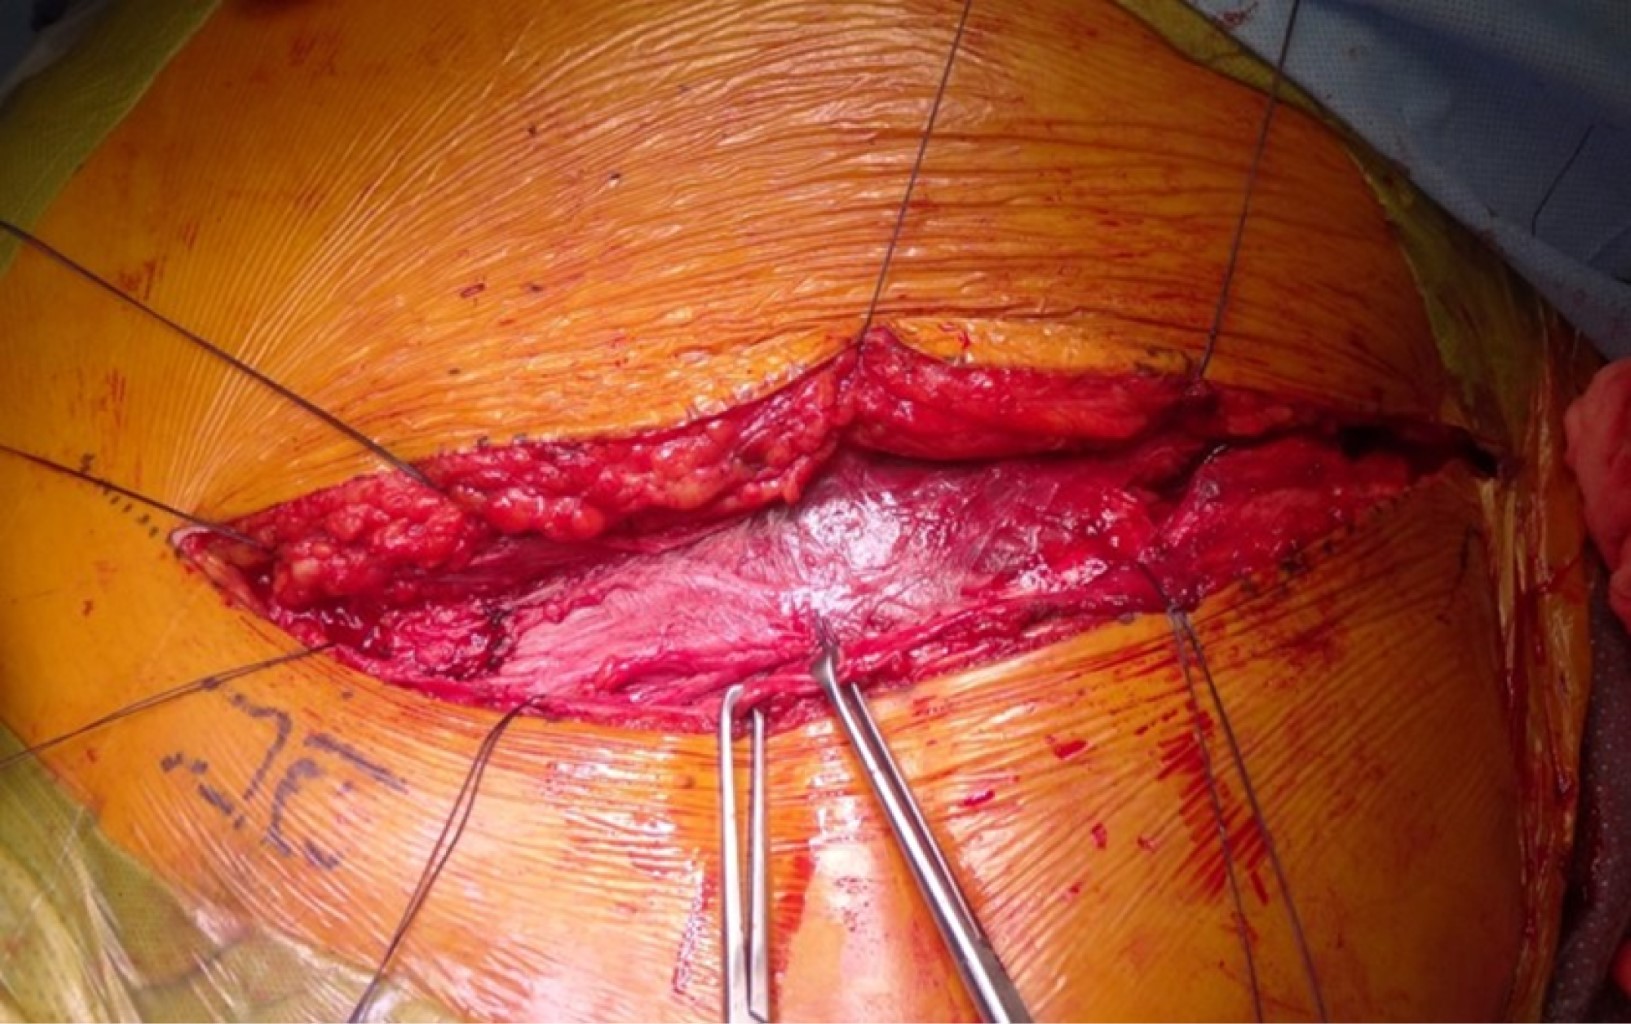

Con el paciente bajo efectos de anestesia se coloca sonda vesical para mantener la vejiga vacía durante todo el procedimiento. Se realiza vestido quirúrgico con cuatro campos separados dejando expuesto el ombligo, ambos flancos y 3 cm distales a la zona de la sínfisis del pubis (Figura 2). Debe planearse para realizar las tres ventanas de trabajo, cuidando las estructuras neurovasculares y realizar la reducción de las fracturas. Es indispensable conocer los patrones de lesión y la clasificación de fracturas acetabulares para determinar que huesos se encuentran afectados y poder decidir que ventanas realizar primero con el fin de disminuir riesgo de sangrado innecesario.11,12

Figura 2